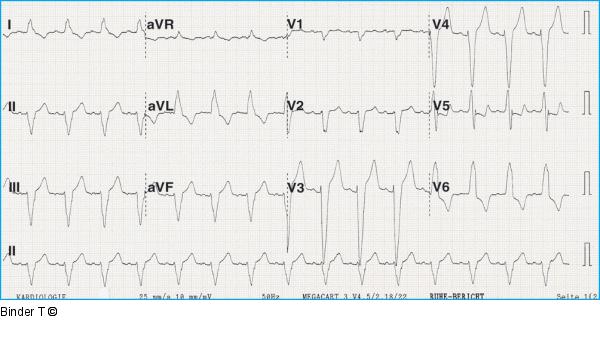

Abbildung 1: EKG